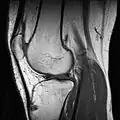

RM de um joelho. -